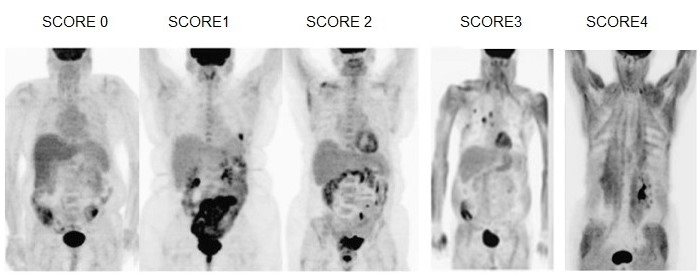

Roy(22) et al. discutem em seu estudo sobre os valores alterados de glicemia e como isso pode influenciar na captação do FGD. Pacientes que apresentam uma glicemia maior que (126 mg/dL) podem apresentar uma redução na sensibilidade do estudo com FDG. Entretanto, pacientes diabéticos que possuem uma glicemia abaixo de (180 mg/dL), apresentam uma biodistribuição adequada do FDG-18F. Os autores classificaram a variação na biodistribuição do FDG em relação à sua captação muscular em diferentes grupos, identificando pontuações entre 0 e 4, demonstrando, portanto, a variação na sensibilidade do método, com o aumento na captação muscular. Na biodistribuição normal, o paciente é identificado com a pontuação 0. Nos casos onde a biodistribuição apresentou alterações, o paciente com captação suave foi identificado com o valor 1; quando a absorção foi muscular, envolvendo mais de um grupo muscular, obteve pontuação 2; nos casos com absorção muscular difusa de intensidade moderada, a pontuação foi 3; e o paciente que apresentou uma absorção muscular difusa e intensa, resultando em exame não diagnosticado, obteve a pontuação máxima que foi 4 (fig. 1). Abaixo, as imagens mostram um exemplo dessa biodistribuição normal e alterada (fig. 2).